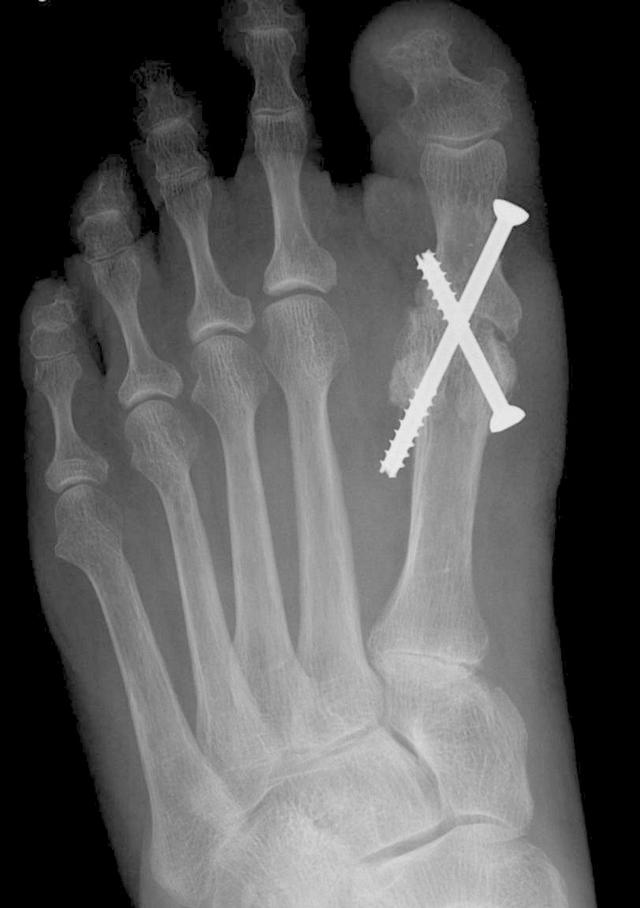

当畸形中等至严重时,Scarf Procedure是常用的选择。从内向外沿跖骨干纵轴截骨。将跖骨头截骨块移向外侧,并用两个螺钉固定。

First Metatarsal-Phalangeal Joint Arthrodesis

永久性的运动消除是该手术是治疗严重畸形的最后选择之一的原因。大多数情况下,还有另一个因素促使选择这种关节破坏性手术:退行性关节炎或关节不稳定。近端指骨正确定位于第一跖骨,然后用螺钉、钢板或交叉的克氏针通过关节固定。